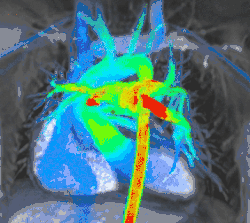

4D flow CMR

Conventional phase contrast imaging can be extended by applying flow-sensitive gradients in 3 orthogonal planes within a 3D volume throughout the cardiac cycle. Such 4D imaging encodes the velocity of flowing blood at each voxel in the volume enabling fluid dynamics to be visualised using specialist software. Applications are in complex congenital heart disease and for research into cardiovascular flow characteristics - however it is not in routine clinical use due to the complexity of post-processing and relatively long acquisition times.[26]